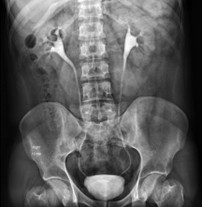

Q32. An urban city has a population of 70,00,000, with 30% residing in slum areas. How many UPHCs are required for the slum population?

- 22

- 32

- 42

- 52

Answer: C